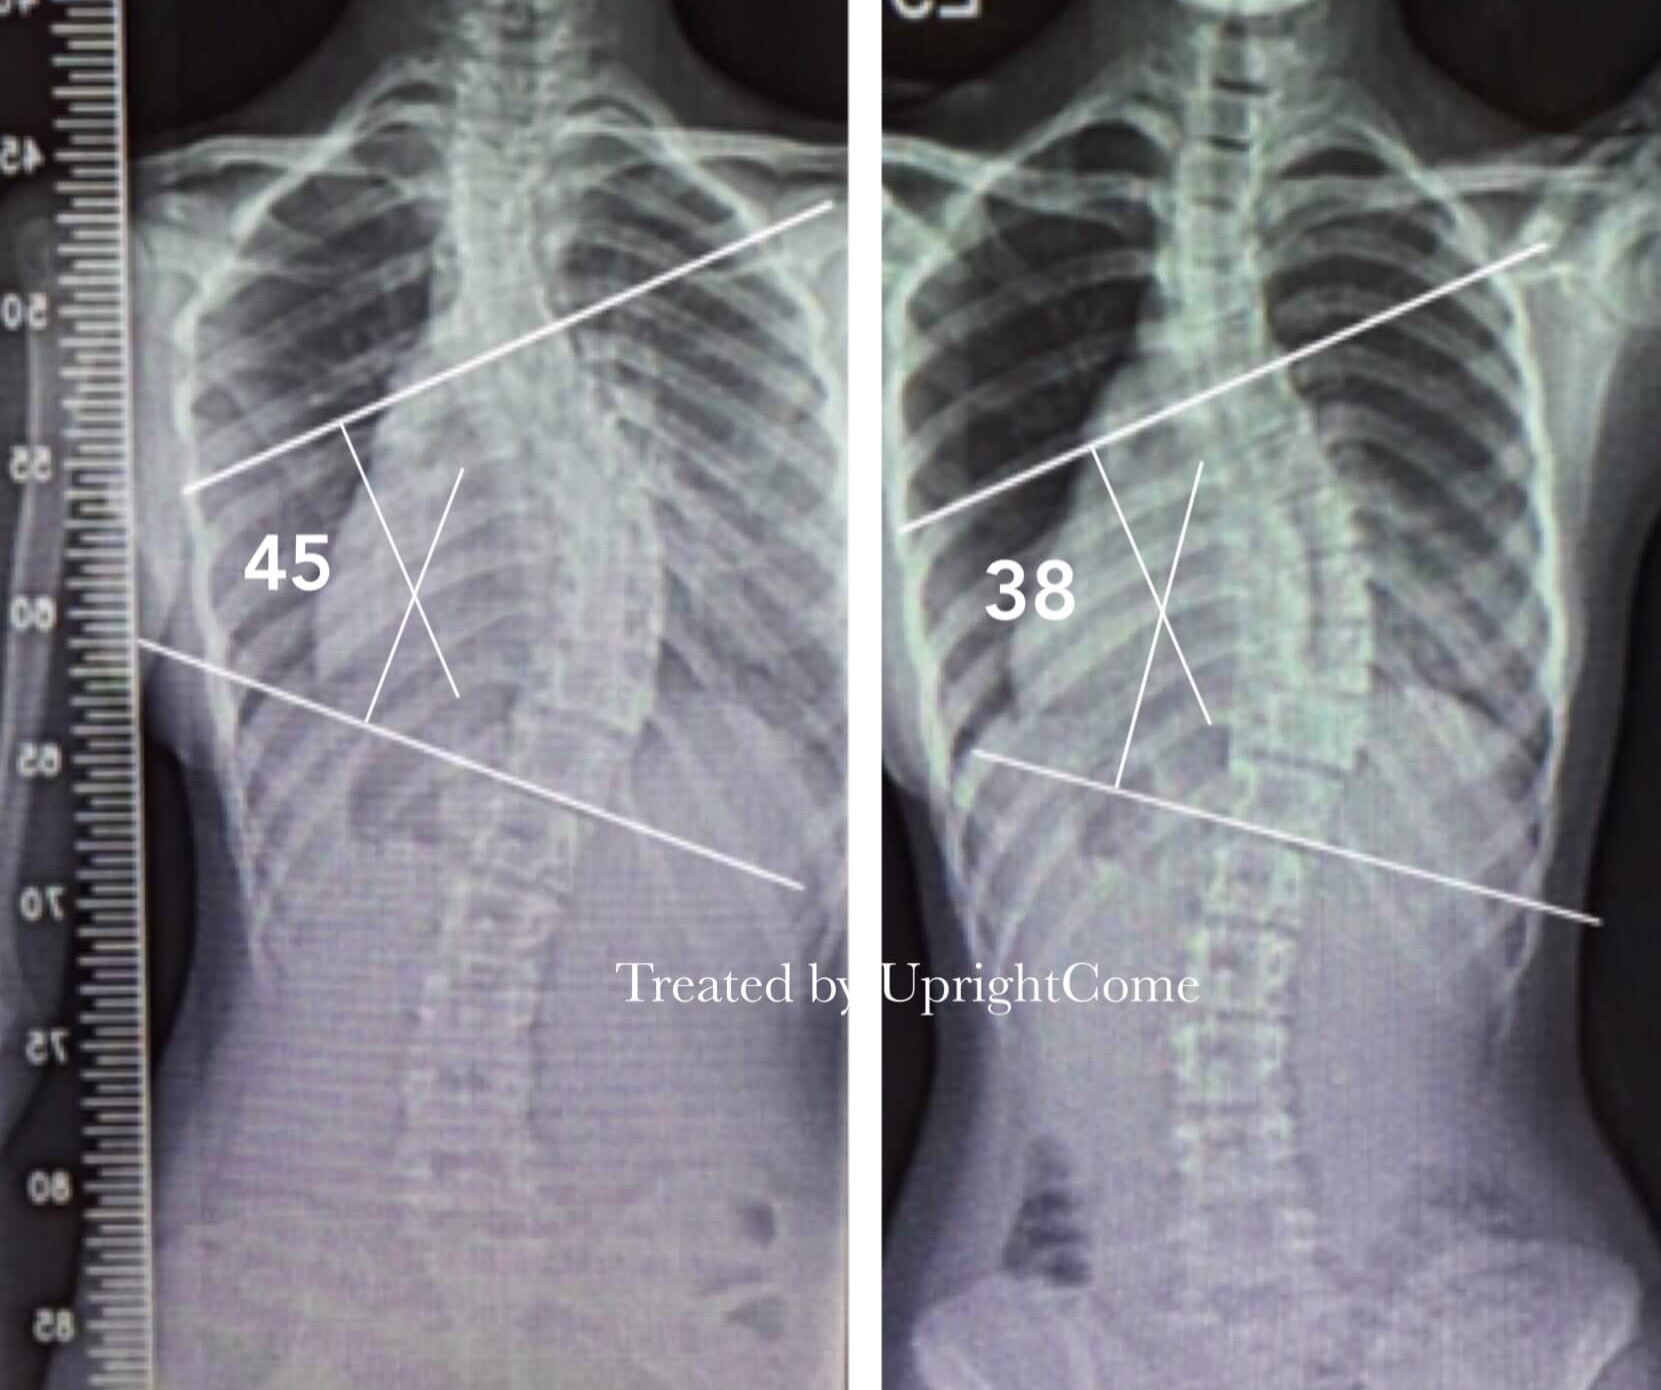

案例 22,17 歲,45 度側彎

![脊椎側彎患者經過側彎矯正治療後,胸椎側彎角度由45度減少到38度。]()

案例 23,21 歲,45 度側彎

![脊椎側彎患者經過側彎矯正治療後,腰椎側彎角度由45度減少到37度。]()